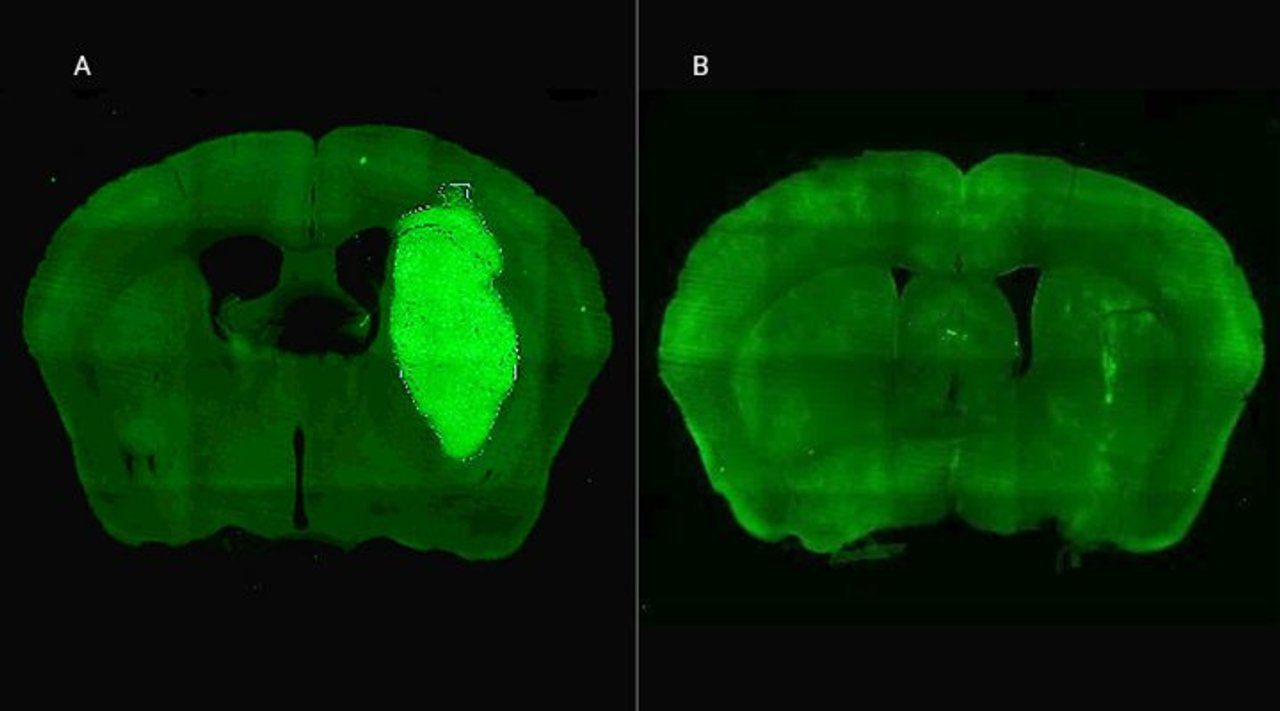

Candolfi y colegas utilizaron una terapia génica experimental basada en una molécula muy pequeña o péptido llamado P60, desarrollado por Juan José Lasarte en la Universidad de Navarra, en España, que atraviesa la membrana celular e inhibe la proteína Foxp3. “Cuando en experimentos de laboratorio bloqueamos Foxp3 utilizando P60, la respuesta de las células de glioblastoma a la radioterapia y a una variedad de drogas quimioterapéuticas mejoró notablemente”, destacó la investigadora del CONICET.

Además, P60 tuvo efectos antitumorales directos, reduciendo la viabilidad y la migración de las células de glioblastoma e inhibiendo la proliferación de células endoteliales que son clave para la progresión del tumor. Para evaluar estos efectos, los autores del estudio utilizaron una variedad de modelos celulares murinos (de roedor) y humanos. “En particular, los cultivos derivados de biopsias de pacientes con glioblastoma desarrollados por nuestro colaborador Guillermo Videla Richardson, del Instituto FLENI, son muy útiles para representar la heterogeneidad de estos tumores”, indicó Candolfi.